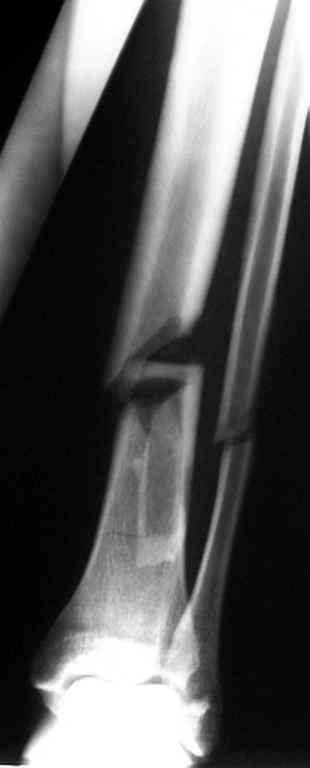

ЮАБ> Хотел-бы услышать Ваше мнение по поводу того, кто как относится к

ЮАБ> наличию свободных осколков в линии перелома и чем при этом

ЮАБ> руководствуется - размер, локализация, возраст и т.д.

Практически единственное, что делает необходимым разрез для манипуляций с промежуточным отломком бедренной кости - это его "застегивание" в илиотибиальном тракте по типу пуговицы в петле.

Когда при движениях в колене этот отломок на сантиметры смещается, создавая очевидный дискомфорт. Даже в этом случае репозиция отломка

именно в его ложе избыточна, достаточно осциллирующей пилой отсечь то, что выстоит над фасцией.

Отломок, расположенный так, как на показанных рентгенограммах бедра, обычно на снимках в 1-2 мес. уже располагается ближе к диафизу и

включается в мозоль.

На голени что-то сделать с отломком вынуждает угроза перфорация кожи, перекрытие отломком входа в канал. Не всегда надо делать разрез, можно и шилом чрескожно фрагмент сдвинуть. Наверно, еще и повреждение сосудистого пучка, когда "виновник" прямо поперек перерезанной артерии и лежит - такое не каждый за всю свою профессиональную жизнь

встретит.

То есть в представленных ситуациях при штифтовании ни на бедре, ни на голени не нужно делать ни открытую, ни закрытую (с помощью шильев,

спиц, еще каких-то "джойстиков") репозицию. Все, что нужно - восстановить ось, длину и ротацию.

Перелом большеберцовой кости почти околосуставный, могут потребоваться дополнительные меры для восстановления оси (отклоняющие спицы или винты), и запирающих винтов в дистальный отломок желательно побольше. Задний край не сломан ли там, не разобрал по этим снимкам.

>Сами собираемся оперировать голень и думаем, что без "открытия" места перелома не обойтись.

"Открытие" "открытию" рознь. Мне видится такая последовательность действий: попытаться установить проводник закрыто на вытяжении или дистракторе. Если прошел -рассверлиться, если нет поправить направление проводника через разрез такой величины, чтобы можно это было сделать но не более того.Если осколок, стремящийся в канал свободен от мягких тканей - удалить его. Удаляли вываливающиеся отломки "перстневидной" формы по более представленного, тем не менее сращение наступало. Если удастся все провести закрыто, манипуляции с отломком нужны, если он будет стремиться перфорировать кожу.Бывает, что для этого не обязательно открываться, просто подтолкнуть осколок через кожу или (цитата:))шилом.